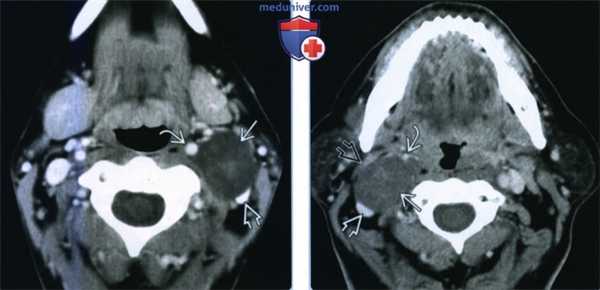

(Слева) КТ с КУ, аксиальная проекция. В левом сонном пространстве визуализируется образование низкой плотности, с небольшим внутренним участком накопления контраста. Внутренняя сонная артерия смещена впереди в медиальную сторону, внутренняя яремная вена - назад и в латеральную сторону.

(Справа) КТ с КУ, аксиальная проекция. Нейрофиброма сонного пространства, плотность которою равна плотности спинного мозга. Накопление контраста минимальное. Внутренняя сонная артерия смещена вперед и в медиальную сторону, внутренняя яремная вена - назад и в латеральную сторону, заднее брюшко двубрюшной мышцы - в латеральную сторону. (Слева) МРТ Т1ВИ FS с КУ, пациент с нейрофиброматозом I типа. В сонном пространстве имеется образование округлой формы, неоднородно накапливающее контраст. Внутреняя сонная артерия смещена кпереди. Внутренняя яремная вена уплощена и смещена вперед и в латеральную сторону.

(Справа) МРТ Т2ВИ в коронарной проекции, этот же пациент. Типичная нейрофиброма блуждающего нерва: удлиненная, овальная форма и неоднородный гиперинтенсивный сигнал. Имеются стигмы нейрофиброматоза I типа: множественные опухоли оболочки спинномозговых нервов.

(Справа) КТ с КУ, аксиальная проекция. Нейрофиброма сонного пространства, плотность которою равна плотности спинного мозга. Накопление контраста минимальное. Внутренняя сонная артерия смещена вперед и в медиальную сторону, внутренняя яремная вена - назад и в латеральную сторону, заднее брюшко двубрюшной мышцы - в латеральную сторону.

(Слева) МРТ Т1ВИ FS с КУ, пациент с нейрофиброматозом I типа. В сонном пространстве имеется образование округлой формы, неоднородно накапливающее контраст. Внутреняя сонная артерия смещена кпереди. Внутренняя яремная вена уплощена и смещена вперед и в латеральную сторону.